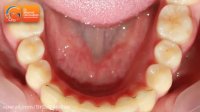

قبل و بعد ارتودنسی نامرتبی دندانهای پایین| دکترداودیان

متخصص ارتودنسی، دکتر داودیان

51 نمایش

7 سال پیش